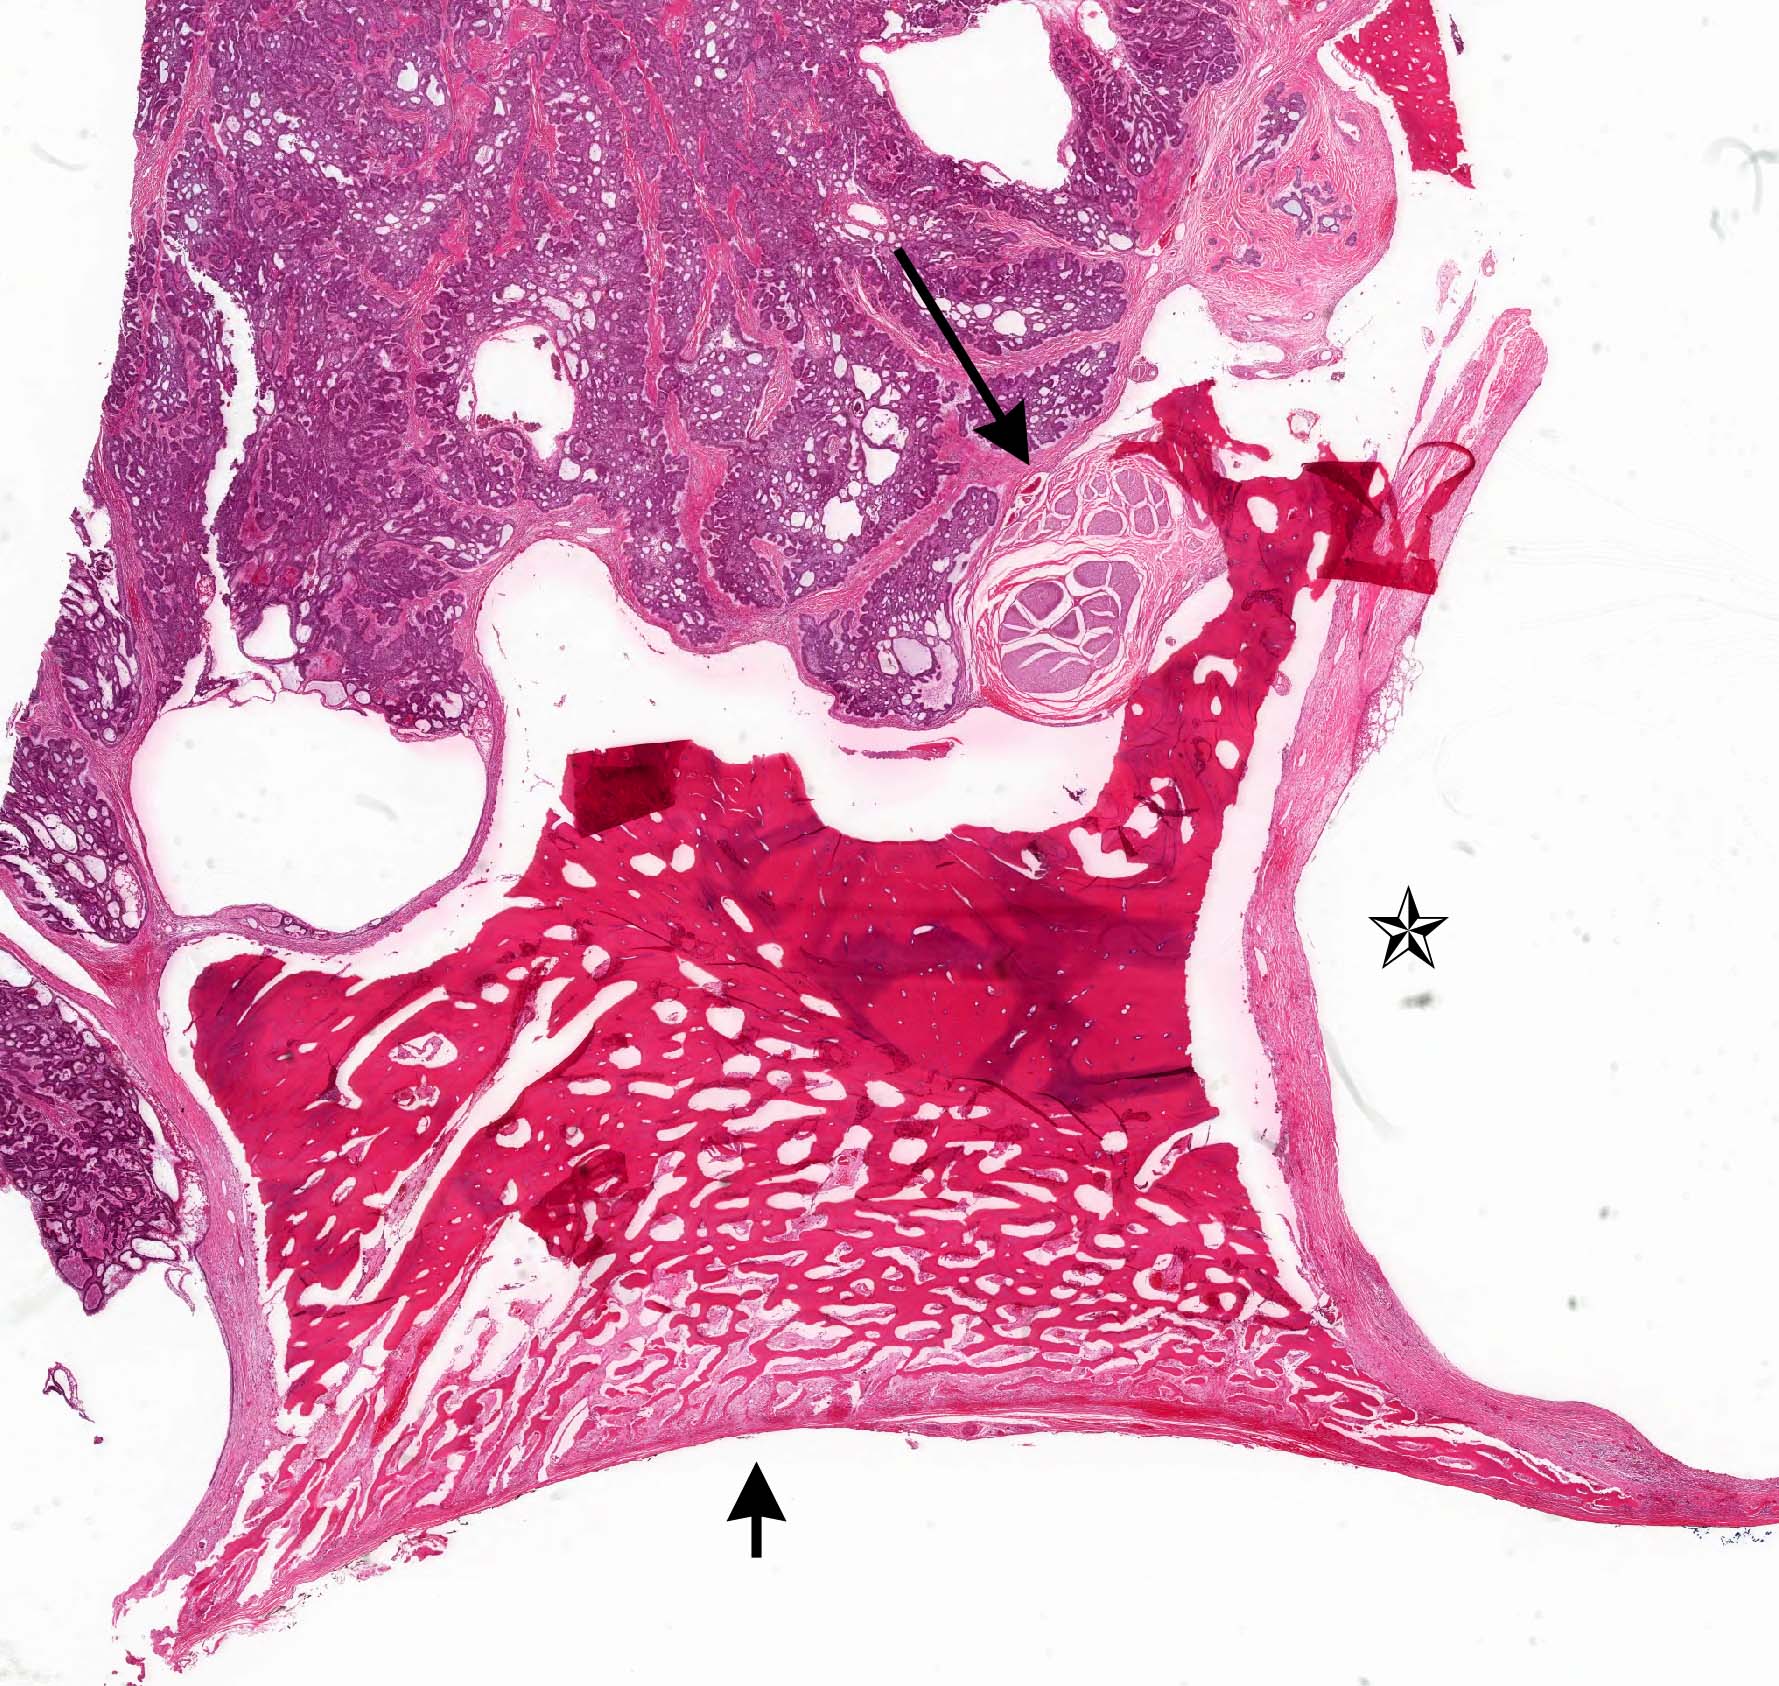

Gross description

- General grossing tips for intraosseous ameloblastoma:

- Prior to sectioning bone, review preoperative radiograph to evaluate for presence and location of any pre-existing metal hardware, titanium dental implants or impacted teeth that could interfere with bone sectioning, could increase difficulty with bone sectioning and be potentially hazardous if unexpectedly encountered

- Ameloblastoma, conventional type:

- Viscous mucoid fluid present on cut surface

- Macrocystic degeneration: larger cystic spaces, may contain clear or red-brown fluid

- Solid, multiple cystic spaces or a combination thereof

- Resorbs tooth roots

- Note expansion or extension beyond bone

- May be associated with impacted tooth

- In mandible, note relation to inferior alveolar nerve if applicable

- Ameloblastoma, unicystic type:

- If surgically removed by enucleation, very little bone may present

- Evaluation of margins precluded by enucleation or curettage type of treatment

- When resected for margins with surrounding bone, unicystic gross appearance is conspicuous and may contain red-brown fluid

- If no mural growth identified on representative sections, consider submitting entire lesion

Gross images

Microscopic (histologic) images

Contributed by Kelly Magliocca, D.D.S., M.P.H. and Anne C. McLean-Holden, D.M.D., M.S.